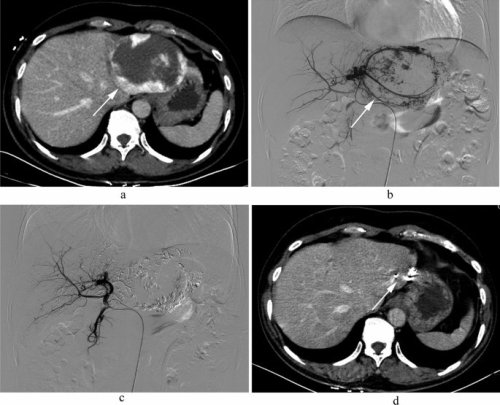

Hình 1: Ekip đang thực hiện nút mạch điều trị u máu gan dưới DSA tại Bệnh viện Ung bướu tỉnh Thanh Hóa

Hình 4. Hình ảnh u máu gan trái trên DSA (b,c) và cắt lớp vi tính trước - sau điều trị (a,d)